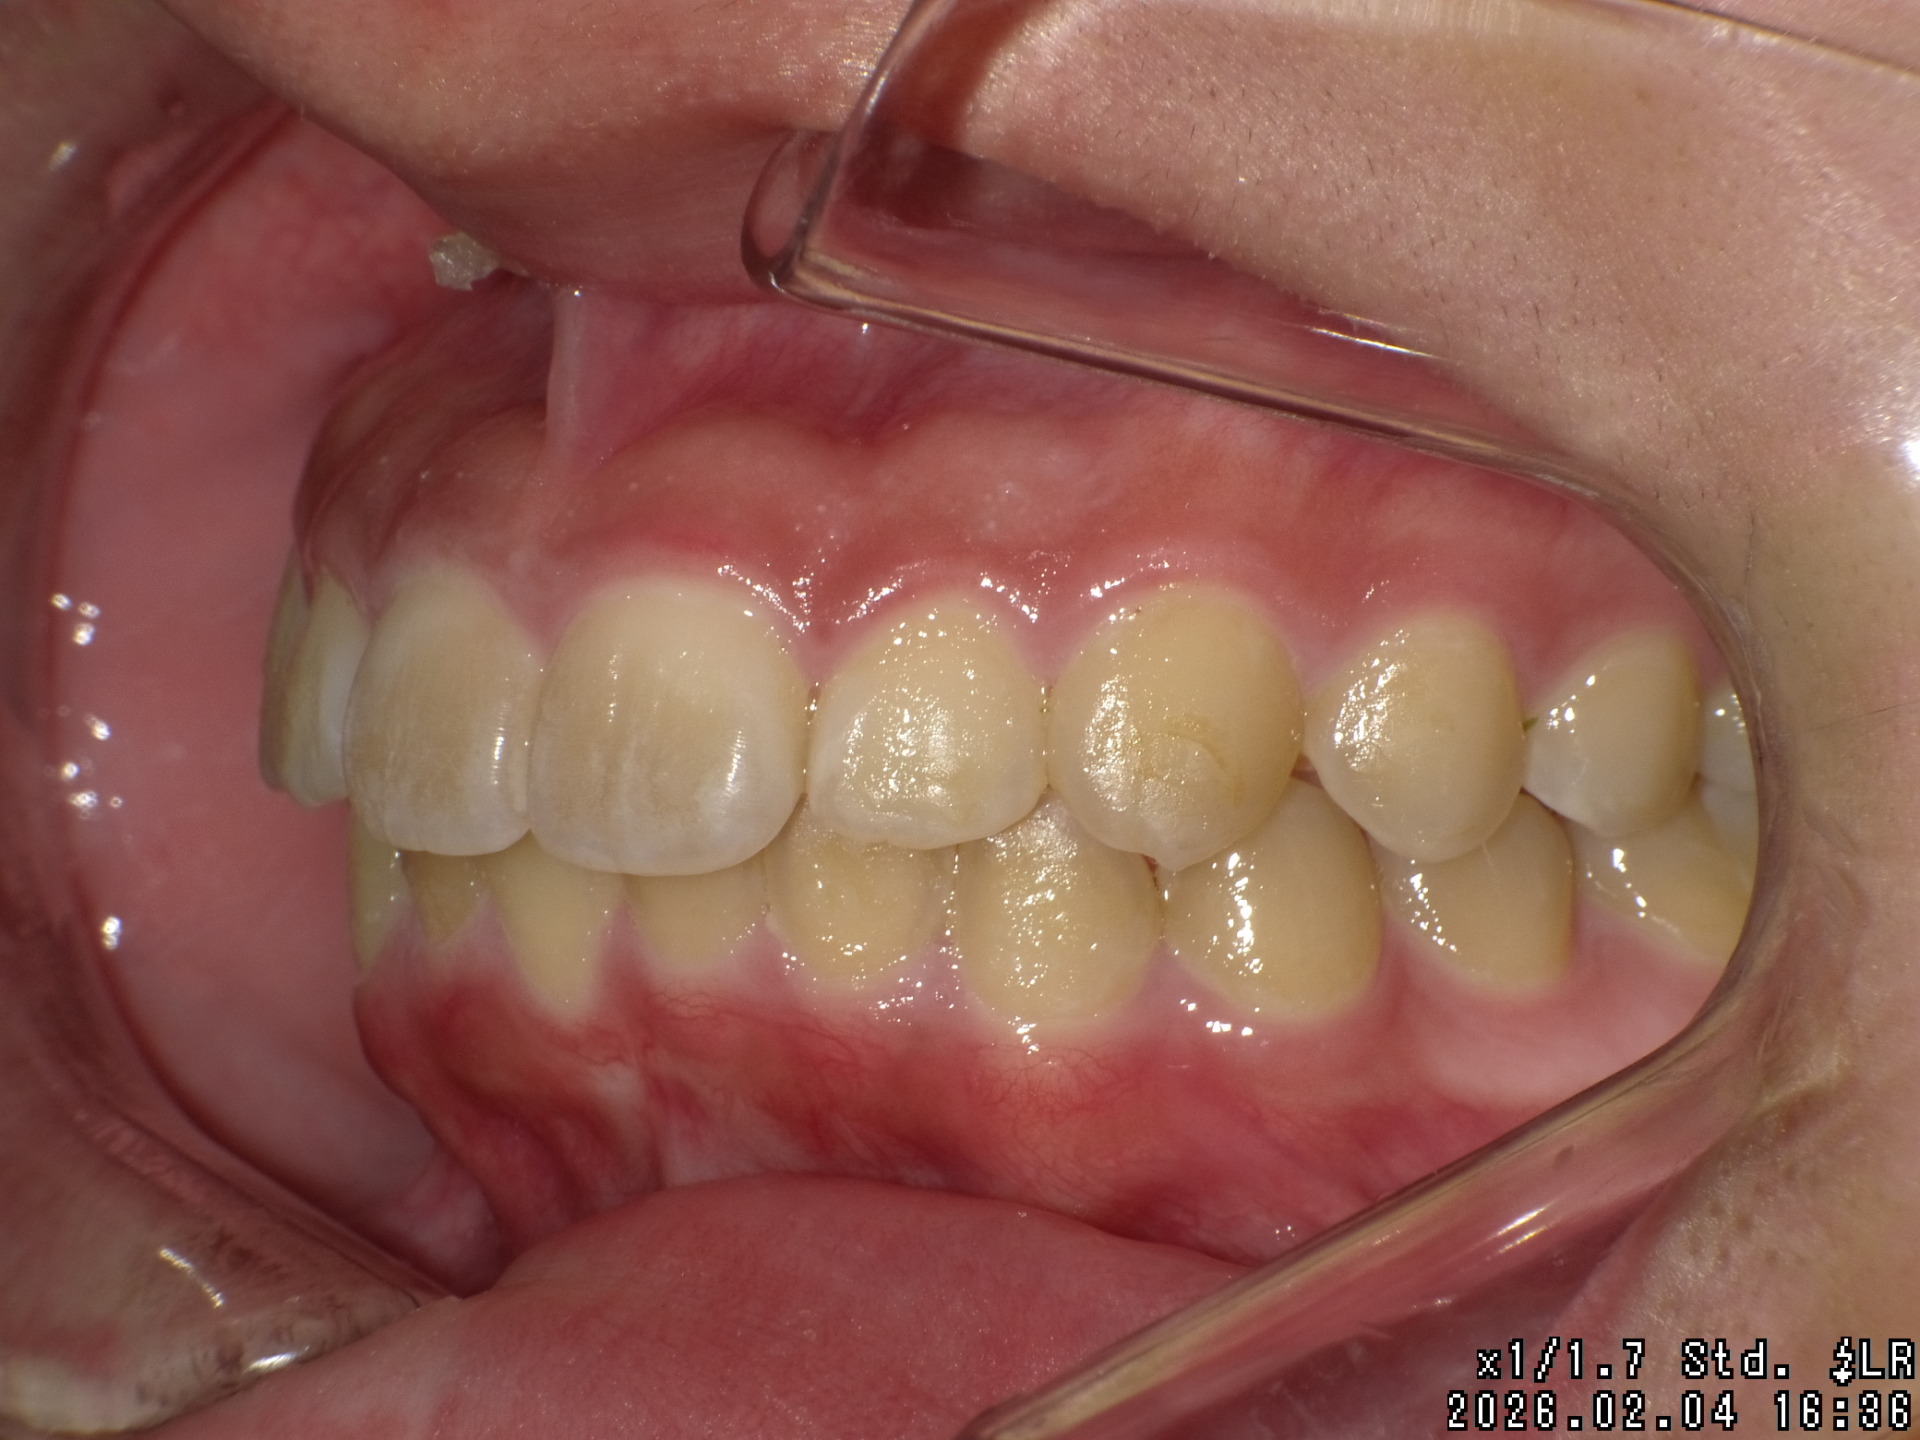

途中経過

| 処置内容 | プレート拡大処置・ディスタライザー・インビザライン・オーソテイン・マルチブラケット装置 |